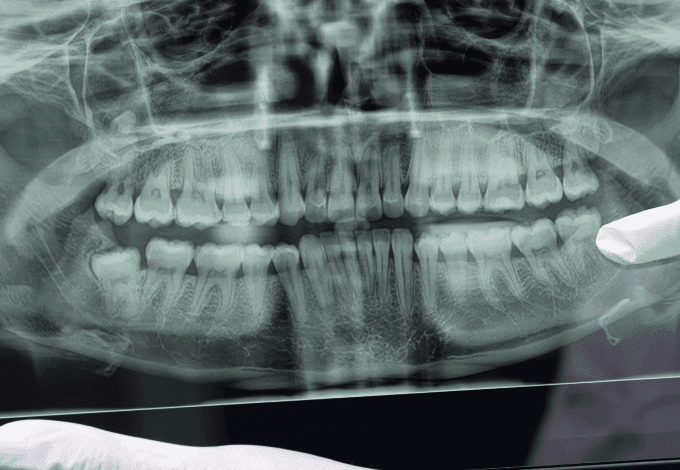

A Dental Speed, em parceria com a ABIMO, marcou presença no evento que movimentou a capital paulista com distribuição de kits e o...